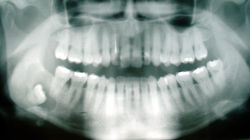

Digital X-Rays

There's a newer dental X-ray technique that our dentist are using, It's called digital imaging. Instead of developing X-ray in a less efficient dark room or processor, the X-rays are sent directly to a computer via a highly sophisticated sensor and can be viewed on screen immediately. There are several benefits of using this new technology:

The technique uses less radiation and there is no wait time for the X-rays to develop

The image taken can be enhanced and enlarged for better diagnostics

This technology can be used for Bitewings, Periapicals and Panoramics